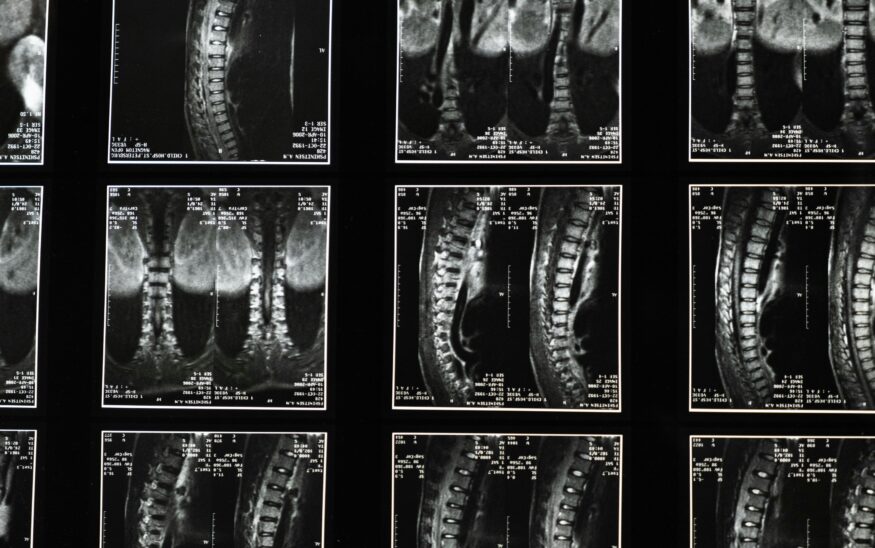

Yet what has not advanced, and what experts say is overlooked danger, is the fact that the imaging technology needed to perform these many life-saving procedures often comes with a hidden, personal cost for medical personnel — radiation exposure.

As an interventional cardiologist, Rizik uses fluoroscopy, which is a real-time X-ray, to place a stent, open a blocked artery, repair a heart valve and close holes in the heart, among other procedures.